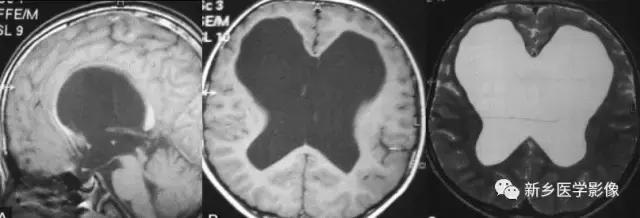

(1)前脑无裂畸形: (holoprosencephaly)是指一系列位于中线程度不同的畸形,累及大脑、面部、脑于和小脑.前脑未能够分开,呈不全性或完全性,端脑和间脑无法区分。根据脑及面部畸形程度将其分为无叶型、半叶型和单叶型。

无叶型前脑无裂畸形最严重.端脑半球间没有裂隙,呈马蹄形或新月形扩大的单脑室跨越中线,与背侧囊交通。丘脑互相融合,面部畸形从两眼距离过近到独眼畸形.往往死于胎儿或新生儿期。

半叶型前脑无裂畸形在前脑可见部分裂隙. 形成不同发育程度的大脑纵裂及大脑镰。两侧大脑半球在前部未完全分开,但枕叶和 双侧侧脑室体部分离,丘脑分开不完全。三脑室和海马发育不全,胼胝体仅可见到压部,而其他部分缺如.额叶和基底节前部分辨不清。临床表现有两眼距离过近.及唇裂、腭裂等面部畸形,侧脑室呈单一性.且明显扩大。

单叶型前脑无裂畸形与正常发育脑仅有些很小的区别.如透明隔缺如或双侧额叶不完全分开。